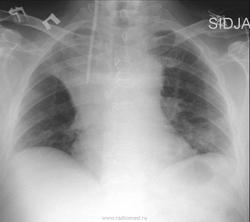

Ателектаз верхней доли правого легкого вижу.Средостение в верхнем отделе расширено.В проекции нижней доли левого легкого -сгущение легочного рисунка? Снимок сделан палатным аппаратом, фокусное расстояние вряд ли выдержано, т.о. оценить размеры сердца не получится.

Интересные версии, а я вот без бокового не могу оценить ничего, кроме расширения верхнего средостения справа с интенсивным затемнением в проекции верхней доли с косой нижней границей, и средней интенсивности овальное затемнение в левом нижнем легочном поле. Где катетер - ну... тут можно гадать сколь угодно, я б указал, что на уровне 4-го грудного позвонка справа в ... см от срединной линии. Мне нужен боковой снимок. И жалобы пациента

Малоизвестный, новый на сайте радиолог Ala определил сразу и точно: "Эктравазация происходит не в плевральную полость, а в клетчатку средостения. Поэтому и не растекается" . Позднее выложенная серия КТ-ушек подтвердила это. Жидкость собралась преимущественно в в/3 переднего средостения, резко сместила латерально медиастинальную плевру, которую Вы принимаете за междолевую плевру. Верхняя доля на месте, но несколько сдавлена и, главное, прикрыта спереди верхней 1/3 переднего средостения.

Эктравазация происходит не в плевральную полость, а в клетчатку средостения. Поэтому и не растекается.

Экстравазация, катетер в загрудинной жировой клетчатке до уровня 8 /?/ грудного позвонка, там же жидкость на протяжении всей грудины. Ателектаза нет. Двусторонний гидроторакс, гипостатическая пневмония слева в S10.

Если бы пациенту можно было сделать рентгенограмму в вертикальном положении, рентгеновская картина была бы иная, и Вы, Kat, ни в коем случае не спутали бы её с Ателектазом.